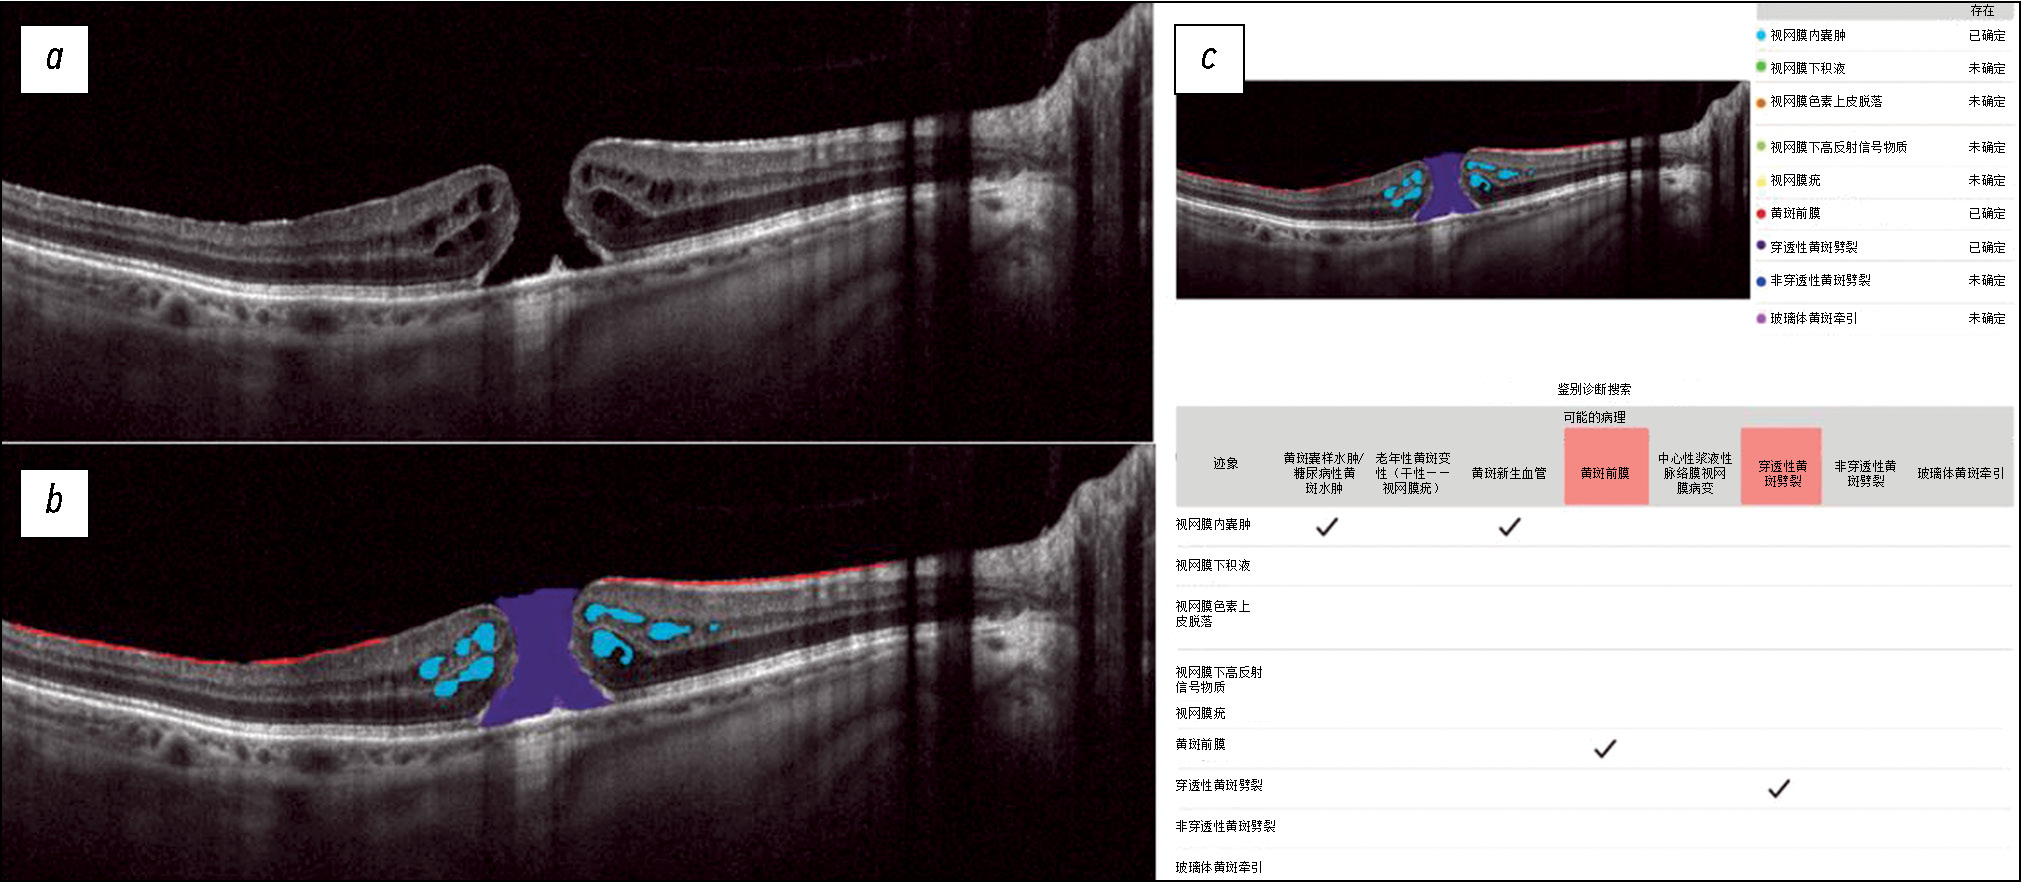

Fig. 3 shows a structural OCT scan of the macular zone of patient K (69 years old) with a full-thickness macular hole diagnosed by an ophthalmologist. In the analysis of the structural OCT scan by Retina.AI, the algorithm segmented the following pathological signs: full-thickness macular hole, intraretinal cysts, and epiretinal membrane. The program report registered a full-thickness macular hole and epiretinal membrane.

Fig. 3. An example of the optical coherence tomography scan analysis of a patient with macular hole, epiretinal membrane by the artificial intelligence algorithm: a — structural optical coherence tomography scan; b — optical coherence tomography scan after segmentation of the pathological features (macular hole — violet mask, intraretinal cysts — blue masks, epiretinal membrane — red masks); c — scan analysis report (the reporting table of the differential diagnostic search, probable pathology is highlighted in red — macular hole, epiretinal membrane).